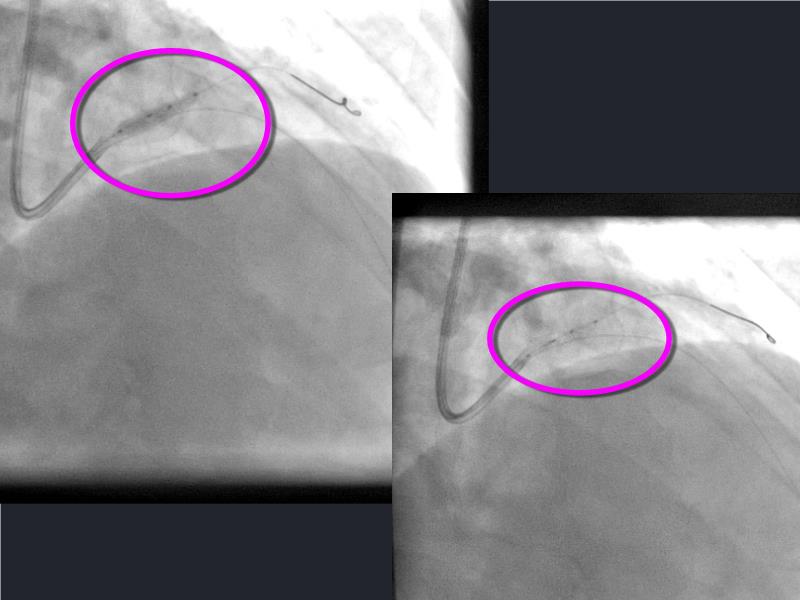

This session is a valuable resource for grasping innovative strategies in handling bifurcation and extended diffuse lesions through dedicated stenting solutions. Explore insights into the advanced Myval next-generation THV technology, unveiling its distinctive features, procedural advantages, and clinical outcomes across a diverse patient pool. Gain understanding into the CorAlign technique, ensuring accurate commissural and coronary alignment while maintaining coronary access. Additionally, delve into the techniques for precise sizing, positioning, and deploying of Myval THV.

- To understand the CorAlign technique which enables predictable and precise commissural and coronary alignment thus preserving coronary access